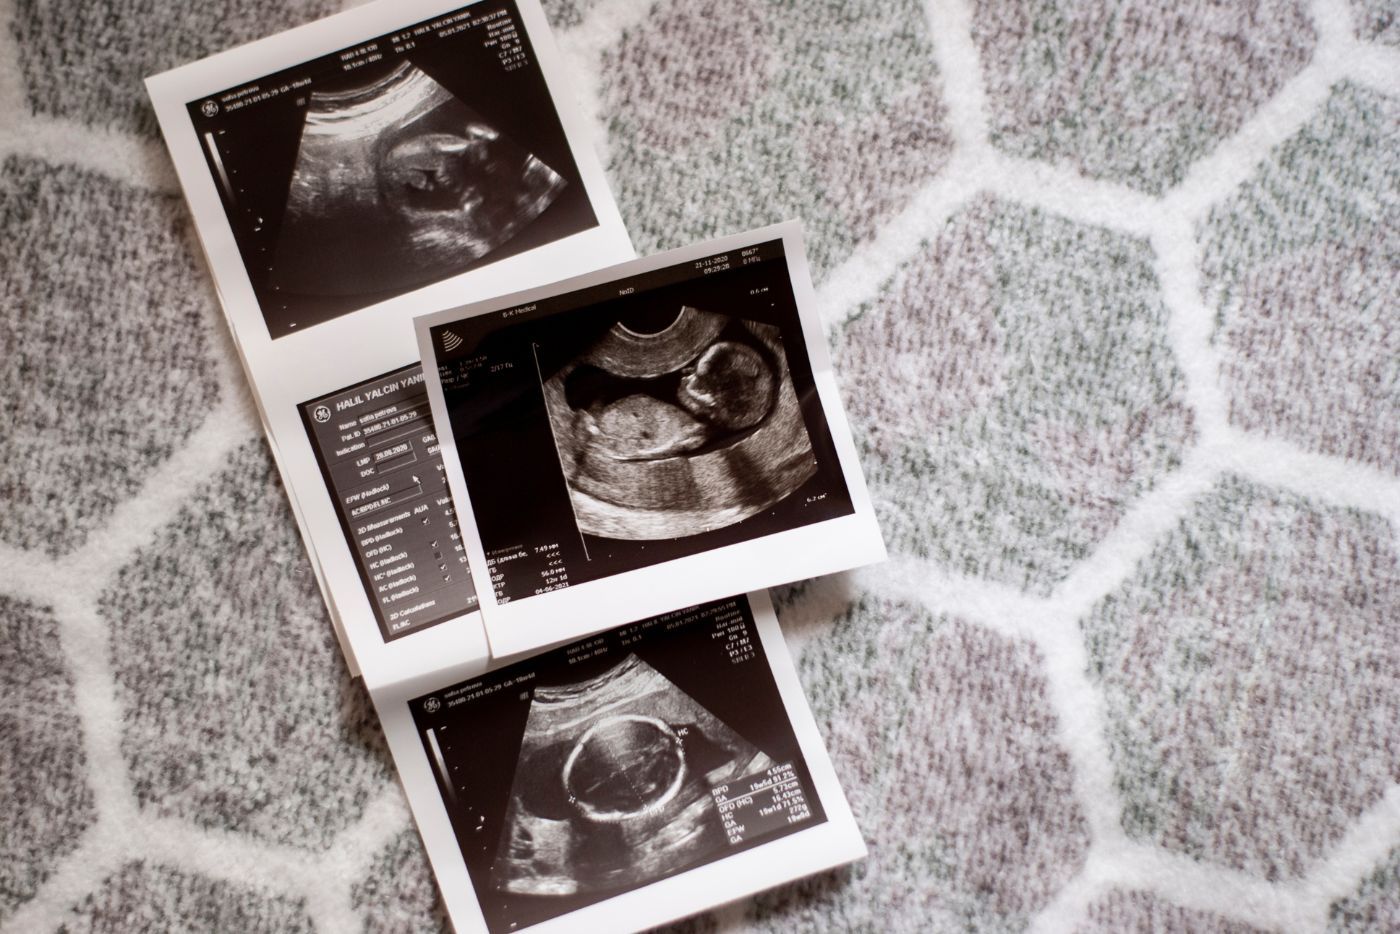

Dari minggu 13 hingga minggu 27 kehamilan (trimester kedua), artikel ini akan menceritakan proses perkembangan janin yang akan berlaku dalam perut si ibu.

Perkembangan janin mengikut minggu kehamilan

Berikut adalah proses perkembangan janin trimester 2 mengikut minggu kehamilan: